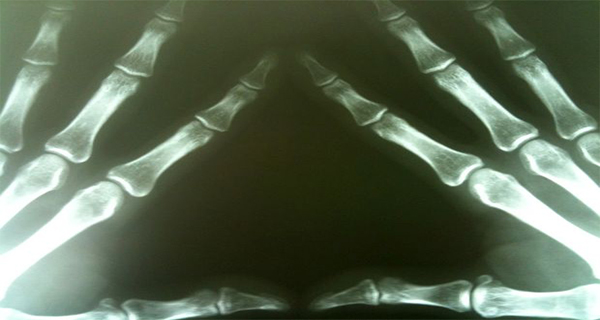

Later in life, your hands will shake. You’ll get arthritis. You’ll suffer from rheumatism… These are just some of the warnings you’ve heard if you often stretch your joints and crack your knuckles. Keep reading to find out what exactly happens.CAUTION Here's What Happens With Your Bones, When You Crack Your Knuckles

The fluid in the joints, synovial fluid, due to the drastic fall in pressure when the wrist is stretched, is converted partly into gas. The sound we hear is actually the gas bubbles coming out of the liquid. Is it safe?